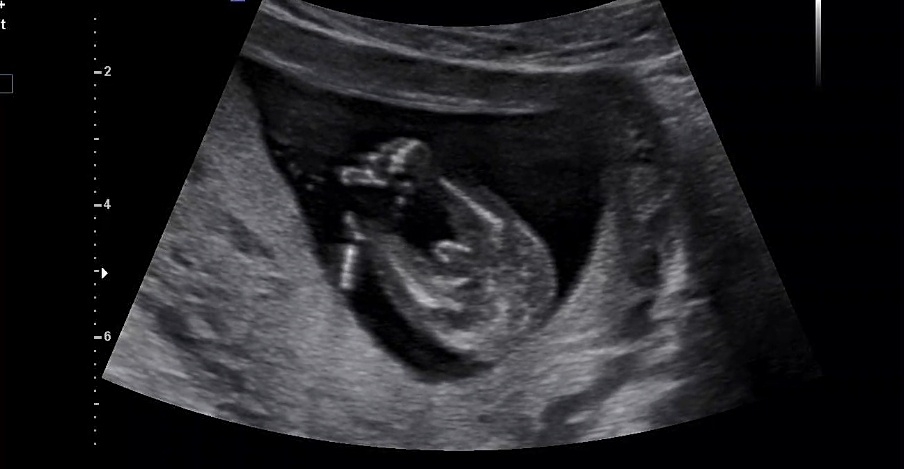

성별반전 가능성 봐주세요15주

성별 한번봐주세요 ㅜㅜ 15주차 반전 기능성있을가요 ???? 여자를 원하는데....슬펏어요 들어가는중 일수 있을가요?

15주면 80% 확정이라고 생각하심 돼요 저희도 15주때 잘은 안보였지만 솟아있다고 말씀하셨었는데 17주때 보니까 아들 확정이였어요 근데 넘 슬퍼마세요 그래도 소중한 아기니까요!!!!